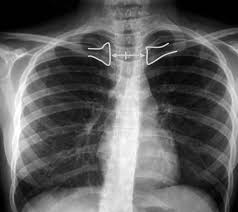

El electrocardiograma (ECG) es una herramienta fundamental en el campo de la medicina cardiovascular, ya que proporciona información crucial sobre la actividad eléctrica del corazón. Este registro gráfico permite detectar…